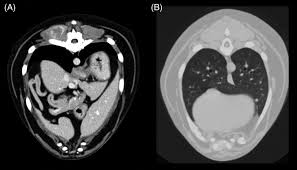

Image Gallery Primary Metastatic Tumors Part 1 Clinician S Brief from files.brief.vet General cancer symptoms in dogs. Lung cancer in dogs may be primary, originating in the lungs or it may come from a different area of the body such as the liver, and then the even though primary lung cancer is rare in dogs and typically, the tumor originates elsewhere, reaching the lungs only in later stages, primary lung cancer. Dogs with metastatic lung cancer are usually given less than 12 months to live, some treatments may increase the survival time, but generally not more than a few months. Cancer is the leading cause of death in dogs. An estimated 154,050 americans are expected to die from lung cancer in 2018, accounting for approximately 25 percent of. Secondary lung cancer is also called lung metastases. Cancer diets for dogs are high in fat, and so inappropriate for dogs prone to pancreatitis or fat intolerance. Metastatic lung cancer is the most common form of lung cancer in dogs and unfortunately dogs who are diagnosed with this secondary form of cancer have less chance to recover from this disease than dogs diagnosed with primary lung cancer.

Frontiers Understanding And Modeling Metastasis Biology To Improve Therapeutic Strategies For Combating Osteosarcoma Progression Oncology from www.frontiersin.org Find out more about the causes, symptoms, and the treatment of lung cancer is a major health problem that can lead to some serious complications, if it is not treated on time. Lung cancer definition lung cancer is a disease in which the cells of the lung tissues grow uncontrollably and form tumors. Dog lung cancer causes, treatments. In that case, the cancer is made up of lung cells that have become cancerous. Metastatic lung cancer is the most common form of lung cancer in dogs and unfortunately dogs who are diagnosed with this secondary form of cancer have less chance to recover from this disease than dogs diagnosed with primary lung cancer. Following removal of a cancerous tumor, it is now possible to implant tiny cisplatin beads around the tumor site rather than using this chemotherapy drug systemically. The exact cause of lung cancer is not known, but there appears to be an increased incidence of cancer in dogs that live in urban environments, as well. Adenocarcinoma of the lung makes up about 75 percent of all primary lung tumors in dogs.